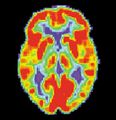

مسح PET لمخ غير مصاب - الصورة مقدمة من مركز الإحالة والتوعية بمرض ألزايمر التابع للمعهد الوطني للشيخوخة بالولايات المتحدة.

مسح PET لمخ مصاب بمرض ألزايمر - الصورة مقدمة من مركز الإحالة والتوعية بمرض ألزايمر التابع للمعهد الوطني للشيخوخة بالولايات المتحدة.